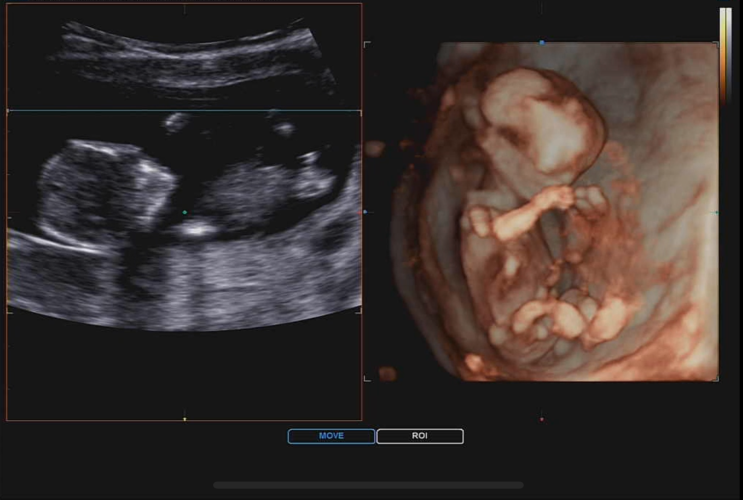

12주 4일 : 1차 기형아 검사, 목투명대 검사, 각도법(이건 누가봐도...?), 입체초음파, 심장소리

임신 중기 임산부 주요 검진 내용 및 주수 10주 이후 : 니프티 검사 가능(고위험 산모의 경우) 12주 : 1차 ...

10주 0일 : 복부 초음파, 젤리곰 시기, 임신초기 입체초음파, 10주차 태아 심장소리

어느 새 10주차 임산부가 되었어요. 그동안 질 초음파로 아가를 확인했지만 드디어 복부 초음파로 아가를 ...